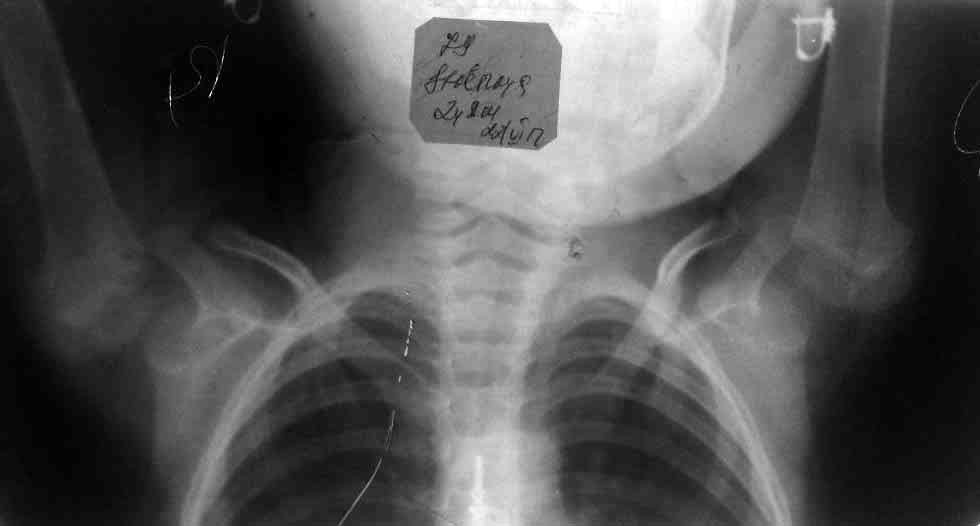

[Ortho] врожденный двухсторонний привычный вывих плеча

вот рентгеннограмма и фото больной